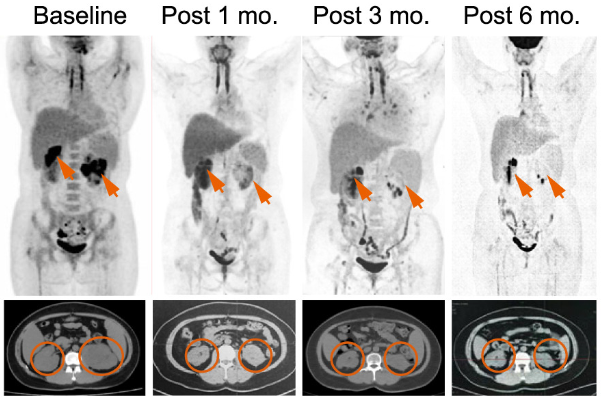

研究结果显示,SPPL3KO/抗CD19 CAR-T细胞疗法在2例R/R大B细胞淋巴瘤(LBCL)患者和1例高危B细胞急性淋巴细胞白血病(B-ALL)患者中均展现出显著的疗效(图4),且CAR-T细胞在3例患者体内均可存活超过6个月(图5)。此外,研究中未出现严重的CRS或ICANS以及急性GvHD反应

图4.其中1例患者SPPL3KO/抗CD19 CAR-T细胞输注前与输注后1、3、6个月的PET-CT